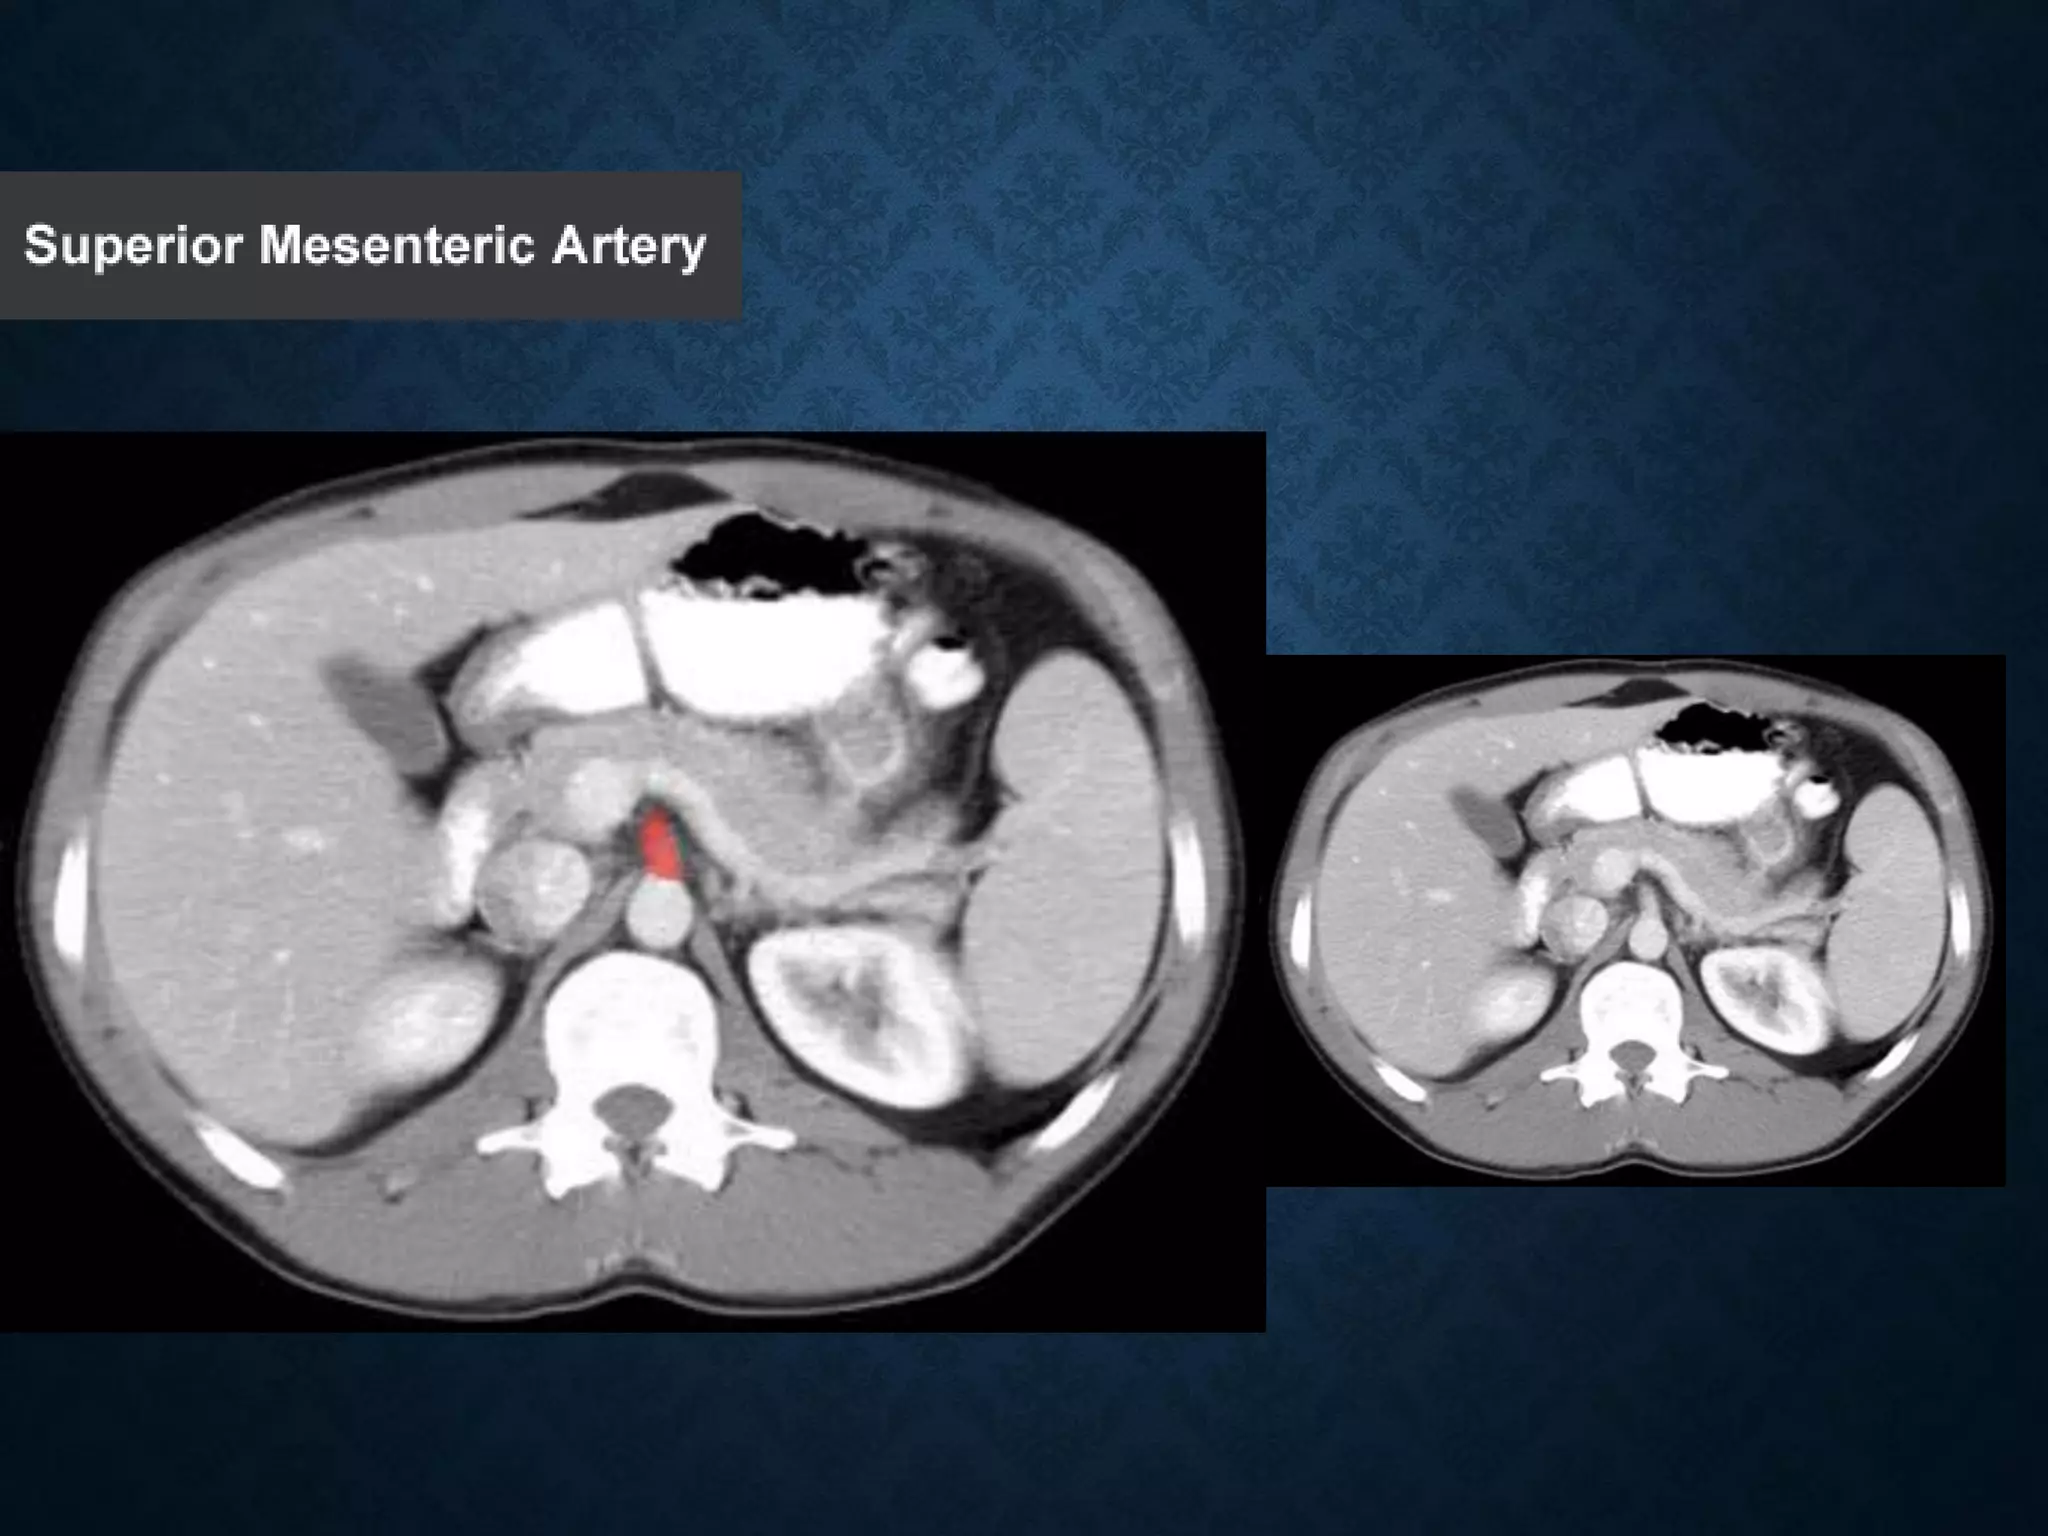

• The SMV lies to the right of the similarly named artery, the superior

mesenteric artery, which originates from the abdominal aorta.

SUPERIOR MESENTERIC VEIN •In anatomy, the superior mesenteric vein (SMV) is a blood vessel that drains blood from the small intestine (jejunum and ileum). • At its termination behind the neck of the pancreas, • the SMV combines with the splenic vein to form the hepatic portal vein. • The SMV lies to the right of the similarly named artery, the superior mesenteric artery, which originates from the abdominal aorta.